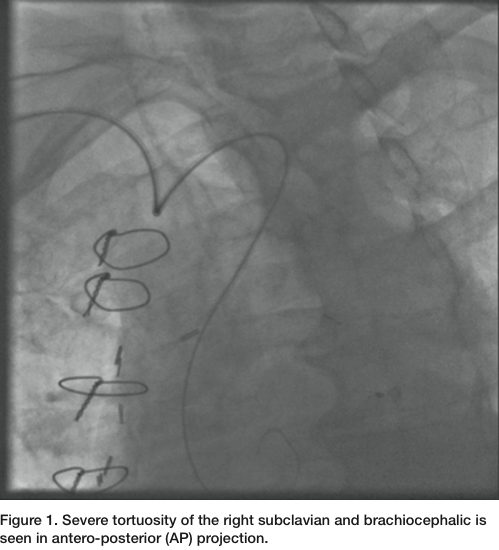

Three months later, the patient presented again with unstable angina. He has been compliant with his clopidogrel and aspirin. He had dynamic ST-T changes, without any elevation of cardiac enzymes. He was brought back to the cardiac catheterization laboratory. Diagnostic images were obtained with Judkins left (JL) 3.5 and Judkins right (JR) 4.0 diagnostic catheters through a 6 French (Fr) Glide sheath (Terumo) access in the right radial artery (RA). The patient had a very tortuous right subclavian and brachiocephalic arteries (Figure 1). The native LAD had a proximal chronic total occlusion. The SVG to LAD demonstrated a patent proximal stent, but with a